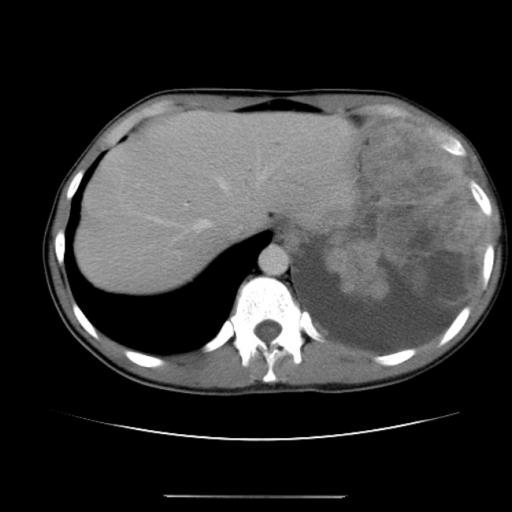

Методы диагностики уплотнения

Возможные процедуры, которые предстоит пройти пациенту:

- УЗИ брюшной полости для определения состояния органов, включая кишечник;

- КТ требуется для просмотра сосудов и тканей кишечника, других органов, иногда применяют процедуру с контрастом;

- колоноскопия назначается при подозрении на патологии кишечника;

- для осмотра желудка назначается диагностика эндоскопическим путем;

- дополнительно назначают сдачу лабораторных анализов;

- при обнаружении опухолевых процессов требуется биопсия материала.

На основе полученных анализов диагноз ставит доктор. Самостоятельно расшифровать результаты невозможно.